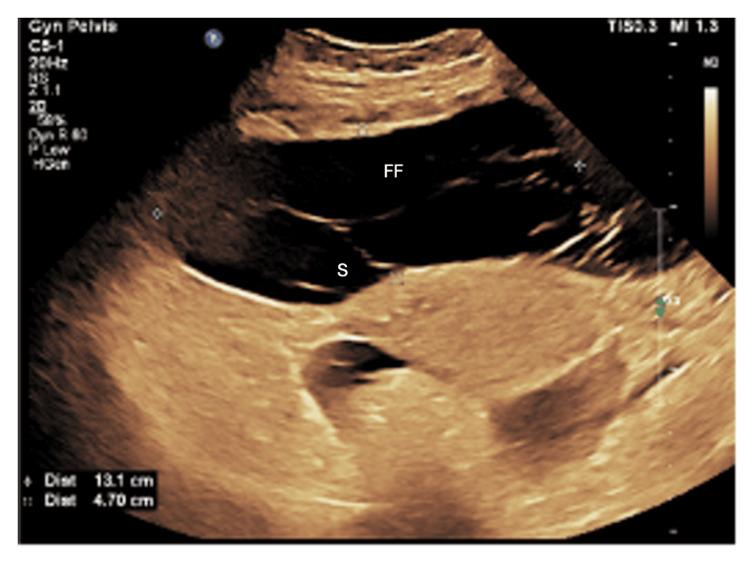

This case report discusses the overall care of a female patient with nephrotic syndrome secondary to non-pre-eclampsia-related hypertension in pregnancy, emphasizing the challenges and multidisciplinary treatment needed for desired results. The case presented here involves a 32-year-old pregnant woman with a history of unexplained primary infertility who conceived through in vitro fertilization (IVF). At 26 weeks and three days of gestation, she presented with symptoms suggestive of nephrotic syndrome, including lower limb swelling, facial puffiness, oliguria, and dark-colored urine. In her history, she had gestational hypertension and was treated with methyldopa. The first presentation and later management of this patient demonstrate the complexities involved in the management of pregnancy complicated by nephrotic syndrome. As part of the diagnostic workup, this patient had a detailed clinical assessment together with laboratory and imaging investigations, which substantiated the diagnosis of nephrotic syndrome. Management of the patient was made complicated by poorly controlled hypertension, the presence of proteinuria, and active inflammation, necessitating combined care by a multidisciplinary team. The management plan, performed at King Abdulaziz Medical City in Riyadh, included close monitoring of maternal and fetal parameters, pharmacological intervention for hypertension and infection, and supportive care to address the symptoms of nephrotic syndrome. This case highlights the complex interplay between nephrotic syndrome and pregnancy, emphasizing the critical need for early diagnosis, multidisciplinary management, and individualized therapeutic strategies. The patient's favorable outcome, achieved through timely intervention (including renal biopsy and emergency cesarean delivery), demonstrates that, even in high-risk scenarios, a coordinated approach can optimize both maternal and fetal outcomes.

本病例报告讨论了一名妊娠合并非子痫前期相关高血压继发肾病综合征的女性患者的整体护理情况,强调了实现预期治疗效果所需应对的挑战及多学科治疗。此处呈现的病例涉及一名32岁孕妇,有不明原因的原发性不孕史,通过体外受精(IVF)受孕。妊娠26周零3天时,她出现了提示肾病综合征的症状,包括下肢肿胀、面部浮肿、少尿和深色尿液。既往史显示她患有妊娠期高血压,曾接受甲基多巴治疗。该患者的首次就诊及后续治疗体现了妊娠合并肾病综合征管理中的复杂性。作为诊断检查的一部分,该患者接受了详细的临床评估以及实验室和影像学检查,证实了肾病综合征的诊断。患者的治疗因高血压控制不佳、蛋白尿的存在以及活动性炎症而变得复杂,需要多学科团队的联合护理。在利雅得的阿卜杜勒阿齐兹国王医疗城实施的管理计划包括密切监测母婴参数、对高血压和感染进行药物干预以及针对肾病综合征症状的支持性护理。本病例突出了肾病综合征与妊娠之间复杂的相互作用,强调了早期诊断、多学科管理和个体化治疗策略的迫切需求。通过及时干预(包括肾活检和紧急剖宫产)取得的良好治疗效果表明,即使在高风险情况下,采取协调一致的方法也可以优化母婴结局。